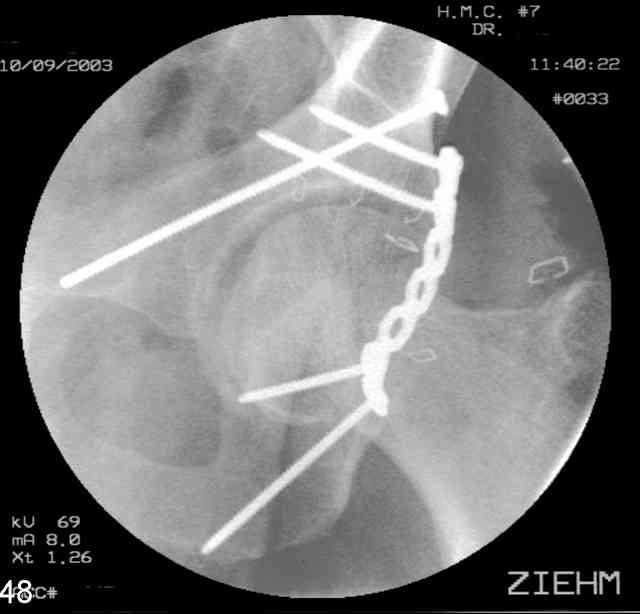

Prone Obturator-Outlet

Screw insertion using the obturator-outlet combination image.

12.Prone Obturator-Outlet

Same with a contoured pelvic reconstruction plate applied and tensioned.

Prone Iliac Oblique

The other oblique reveals the extra-articular implants.... you know the AC screw is extra-articular from the other views.